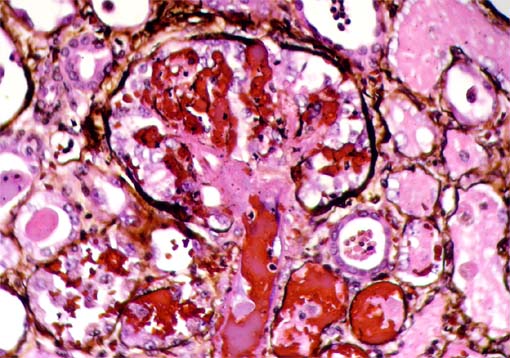

En el caso que presentamos el compromiso vascular es evidenciado también por necrosis hemorrágica del parénquima (ver la Figura 11, abajo). Con la tinción de plata metenamina se ven mejor los microtrombos (Ver Figura 12, abajo).

Figura 12. Plata metenamina, X400..